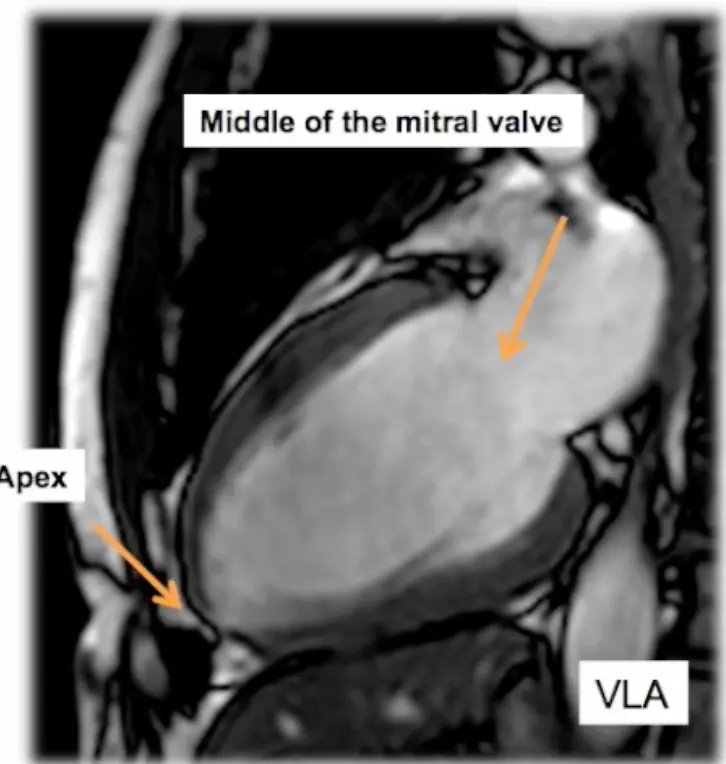

- We begin with the transverse LAX view and position the line marker dissecting the apex and the middle of the mitral valve (where the two leaflets meet) → results in a vertical LAX (VLA) view, aka pseudo 2 chamber (p2CH) view

- Next we slice the resulting VLA view: again, we cut across the apex and the middle of the mitral valve (where the two leaflets meet) → results in a horizontal LAX (HLA) view

- Resulting scout views include VLA and HLA views